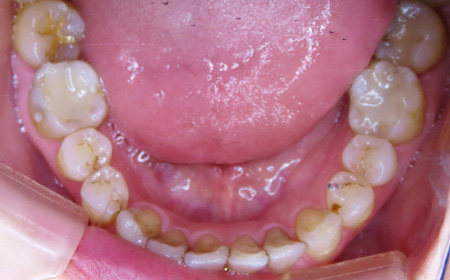

CASE01

Before

After